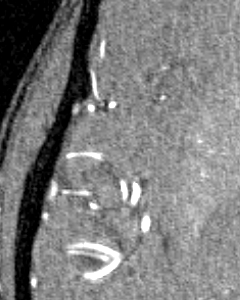

Vessel segmentation is an essential task in many clinical applications. Although supervised methods have achieved state-of-art performance, acquiring expert annotation is laborious and mostly limited for two-dimensional datasets with a small sample size. On the contrary, unsupervised methods rely on handcrafted features to detect tube-like structures such as vessels. However, those methods require complex pipelines involving several hyper-parameters and design choices rendering the procedure sensitive, dataset-specific, and not generalizable. We propose a self-supervised method with a limited number of hyper-parameters that is generalizable across modalities. Our method uses tube-like structure properties, such as connectivity, profile consistency, and bifurcation, to introduce inductive bias into a learning algorithm. To model those properties, we generate a vector field that we refer to as a flow. Our experiments on various public datasets in 2D and 3D show that our method performs better than unsupervised methods while learning useful transferable features from unlabeled data. Unlike generic self-supervised methods, the learned features learn vessel-relevant features that are transferable for supervised approaches, which is essential when the number of annotated data is limited.